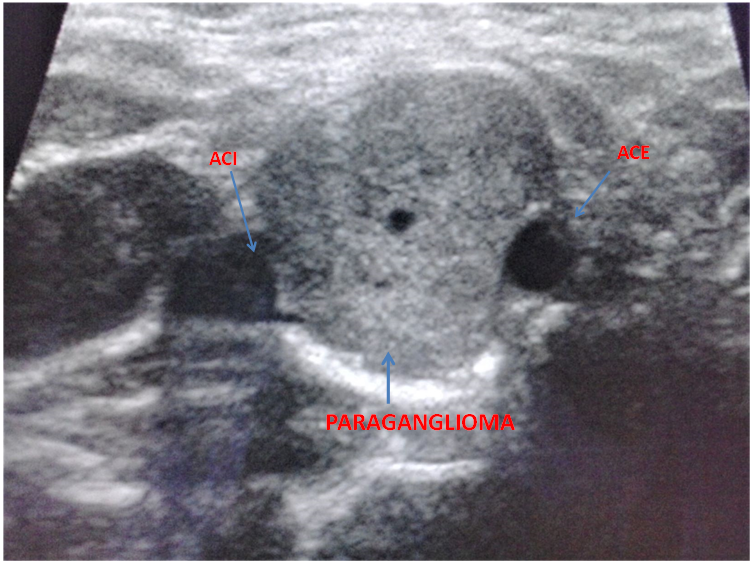

A 31-years old caucasian man came to the neurology emergency department because of the sudden onset of right-sided palsy with sluttered speech. He reported no headache, dizziness or convulsions. After the initial workup, he was admitted to the neurology department. MRI showed subacute ischemic stroke in the posterior part od left insula and operculum. 3D- TOF MR angiography showed occlusion of one of the smaller branches in M2/M3 segment. We performed a doppler ultrasound of carotid and vertebral arteries that indicated vascularized parenchymal structure between ACI and ACE on the right side (Figure 1). Because of that, we did MRI of the neck that verified the inhomogenic structure at the bifurcation of carotid arteries od the right side, dimensions 2,6X1,8X1,9cm that resembles paraganglioma (Figure 2).

Figure 2 MRI of the patients neck showing large paraganglioma between internal and external carotid arteries.